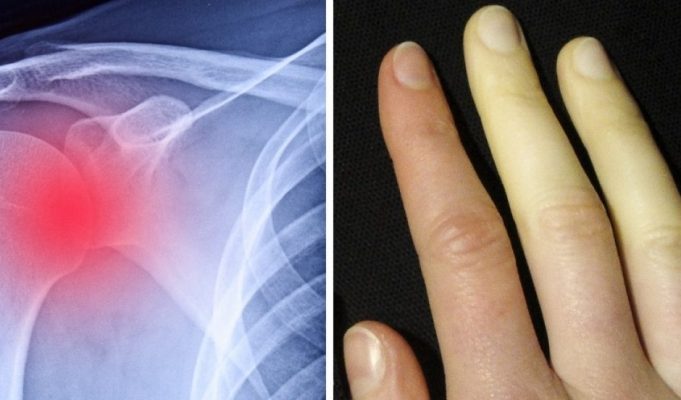

İnflamasyon Nedir? İnflamasyon Belirtileri, Nedenleri ve Tedavisi